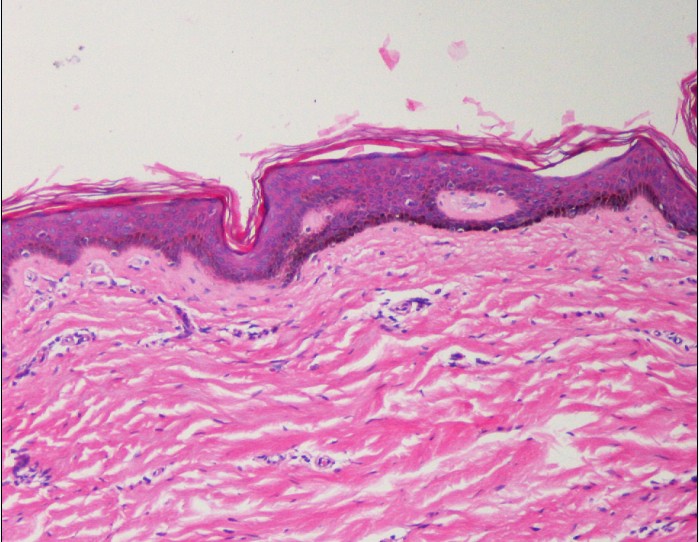

ÈËÆ¤·ôHEȾɫ£¬ÎªÊ²Ã´¿´²»µ½»ùµ×Ĥ£¬È¾ºÃÁËÊDz»ÊǺìÉ«µÄÒ»ÌõÏߣ¿

ÎÒÕâ¸öºÃÏñÖ»ÊÇÕâ²ãϸ°û×ÅÉ«±È½ÏÉÔõô»ØÊ£¿

»¹ÓУ¬ÎªÊ²Ã´Õâ²ã°¼Í¹²»Æ½µÄ£¬ÎÒ¿´±ðÈ˵ͼ±È½Ïƽ

400¡Á

200¡Á

×î½üÔÚ×öÕâ¸ö¡£¿´ÁËЩÎÄÏ×£¬°¼½øÈ¥µÄÓ¦¸ÃÊÇëÄÒ°É¡£